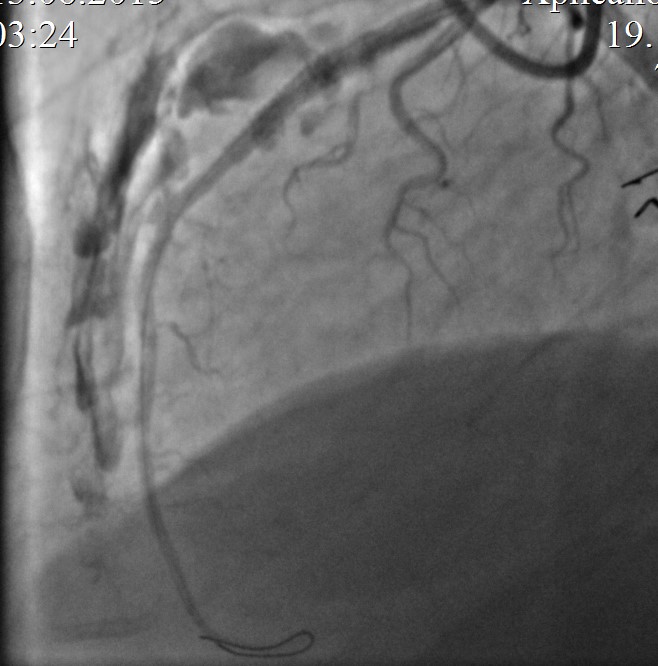

На КАГ: ПМЖА – устье кальцинированный стеноз 50%, среднем отделе кальцинированный протяженный стеноз 99% с переходом в кальцинированную окклюзию, дистальный кровоток TIMI 0-I. (в последующем наблюдается спонтанная реканализация перед ЧКВ, с кровотоком TIMI II-III). Дистальные отделы заполняются фрагментарно ретроградно из ветвей ПКА. ПКА проксимальном отделе стеноз 40%.

Контрольная КАГ: просвет ПМЖА в зоне вмешательства полностью восстановлен, остаточный жесткий кальцинированный стеноз среднего отдела стентированного сегмента 50%, антеградный кровоток TIMI III на протяжении по всем артериям.

Контрольная КАГ: среднем отделе выраженная экстравазация контраста, (III тип по Ellis – в анатомическую полость).